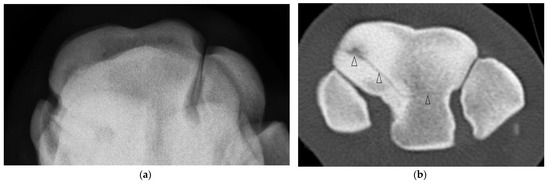

Of the five horses with incomplete, frontal, RaF Fx, one was not evident radiographically and CT was performed due to undiagnosed carpal lameness. On DR of this horse, severe sclerosis of the dorsomedial aspect of the RaF, mild modelling of distal dorsal aspect of Cr and mild entheseous new bone (‘carpitis’) of Cr were reported. CT revealed a subtle, linear, frontal radiolucency within the dorsomedial aspect of the RaF, modelling or osteophytosis (OP) at the C2-C3 articulation and changes within Cr (Figure 2, Supplementary Figure S2). Marked sclerosis was also a feature of the other cases, as were DCL that were more evident on CT than DR (Supplementary Figure S3) and/or mild entheseous new bone Cr, and additional lesions including OF of distal Cr (diCr) and SCBL with vague vertical lucencies that extended into the trabecular bone of diCr not detected on DR (Figure 2).

Figure 2. Images of the left carpus of a 3-year-old thoroughbred colt. (a) Flexed dorsoproximal-dorsodistal oblique radiographic view of the distal row of carpal bones. There is moderate sclerosis of the radial facet of the third carpal bone (C3). (b) Transverse and (c) sagittal CT images of the left carpus reveal an incomplete frontal fracture of the radial facet (arrow heads) that was not evident radiographically. (d) Within the radiocarpal bone there is a subchondral lucency approximately 4 mm from the dorsal articular margin, vague vertical lucencies that extend into the trabecular bone (arrows) and surrounding sclerosis.